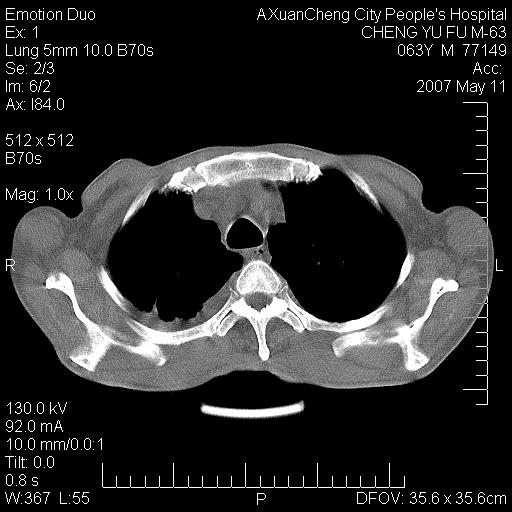

以下是引用小初学者在2007-5-11 19:32:00的发言:[br]1、首先考虑干酪性肺炎支气管播散[br]2、支气管肺泡癌待排

以下是引用zhangzhongshou在2007-5-11 19:30:00的发言:[br]细支气管肺泡癌可能性大。